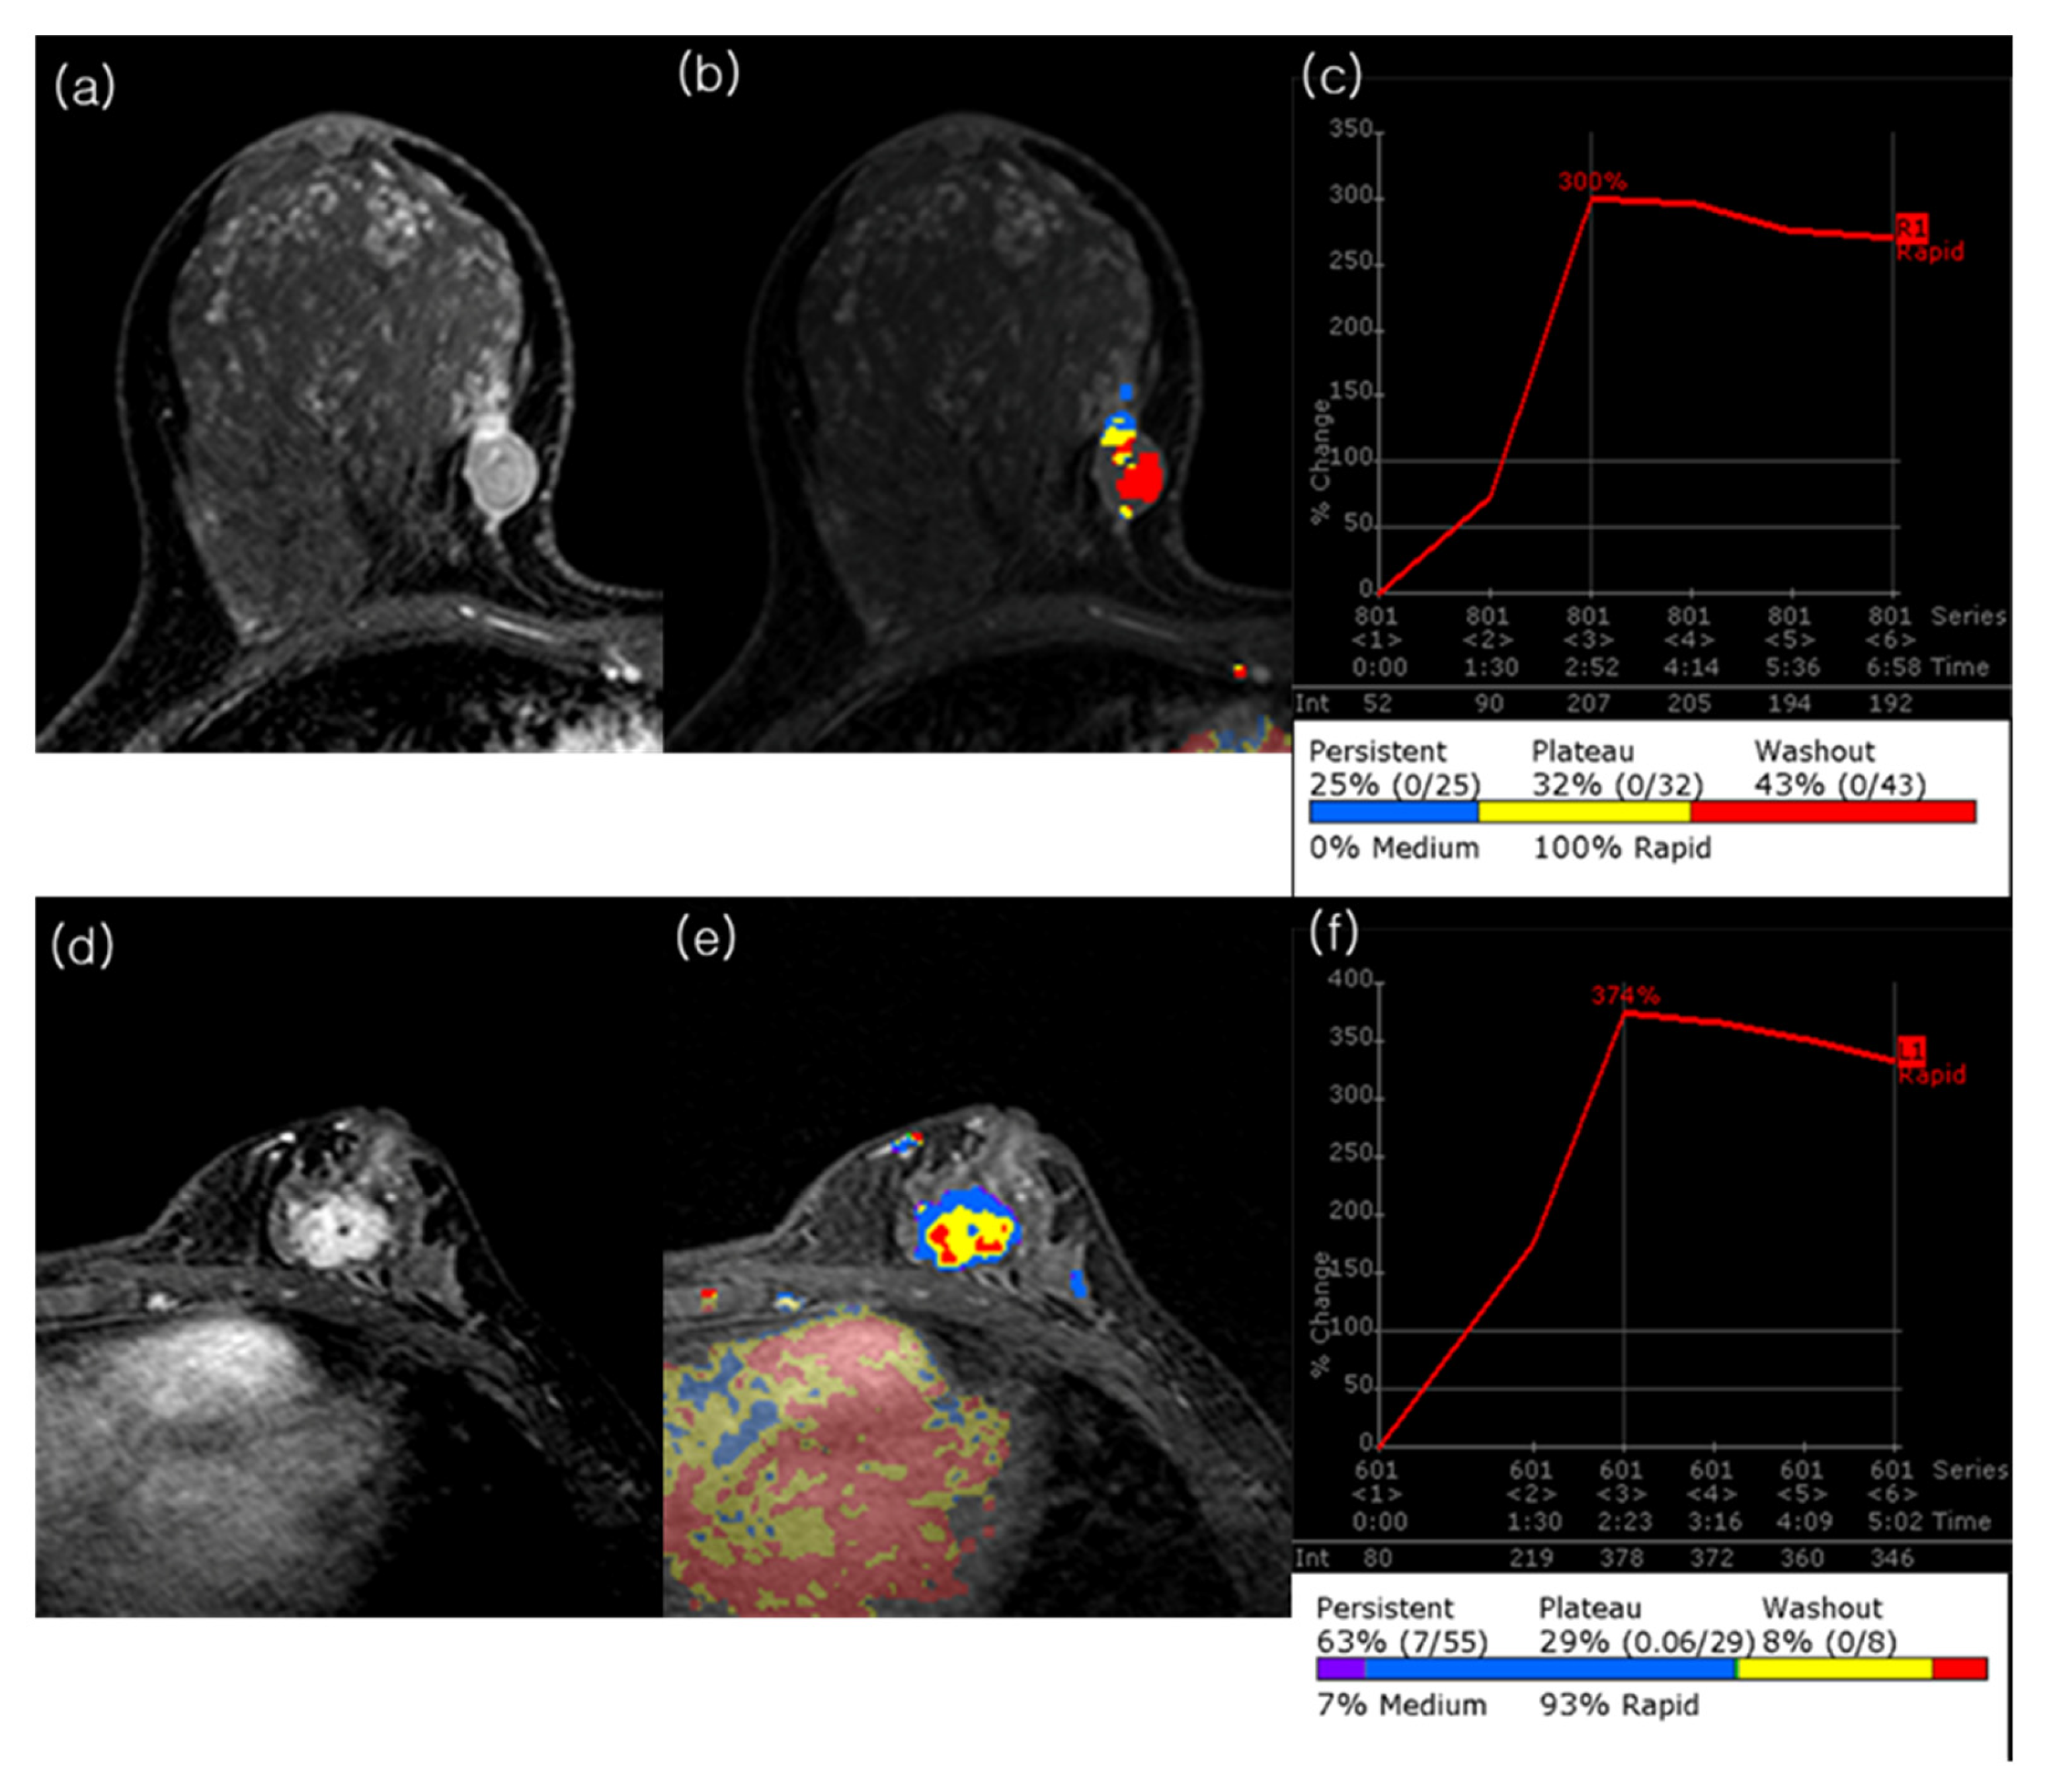

2.3. MRI Analysis